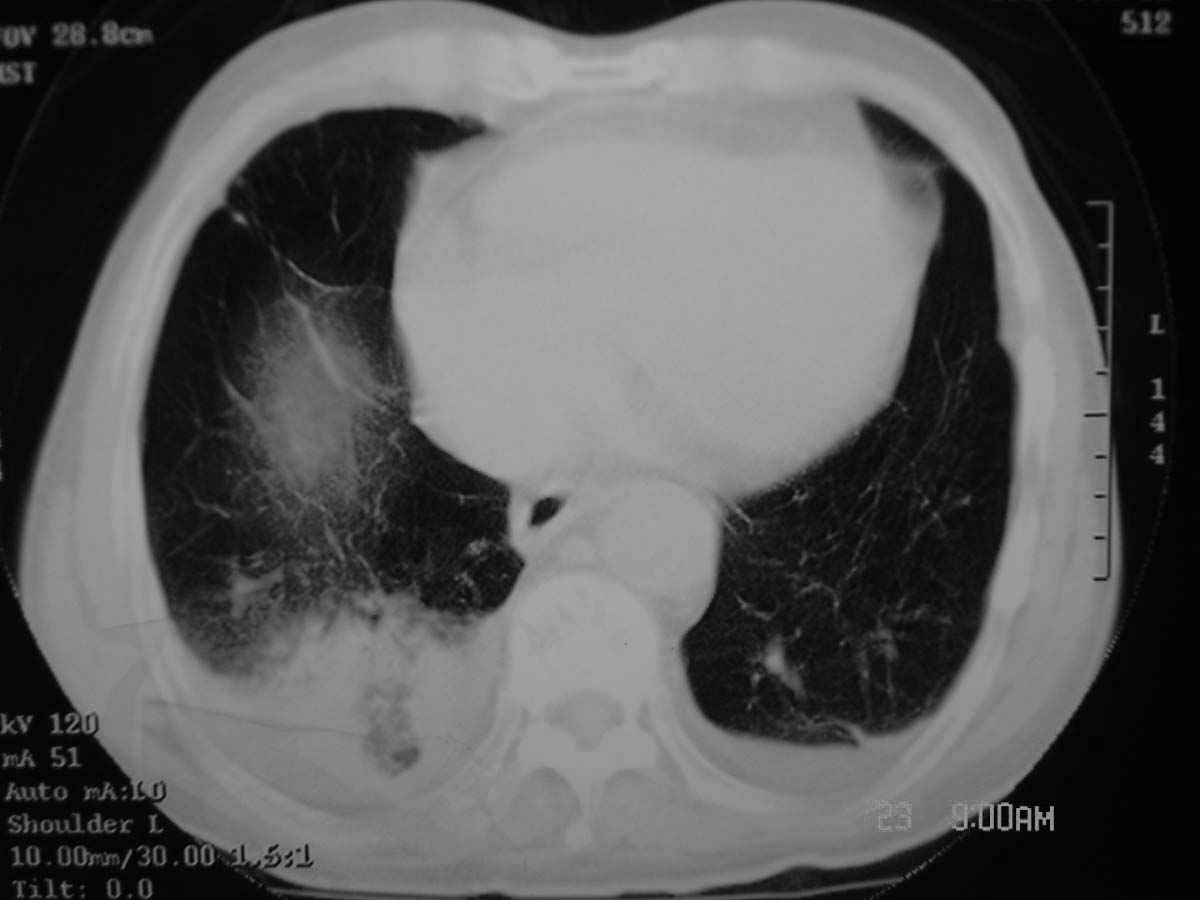

以下是引用守望可可西里在2006-11-23 14:33:00的发言:[br][br] 糖尿病病人很容易继发结核,病人又有双侧胸膜增厚、粘连、胸腔积液以及双上肺的斑片状、条索状影结核病灶影,以一元论考虑,右下肺病变首先考虑干酪性肺炎,可以正规抗炎治疗后复查,排除一般的肺炎。